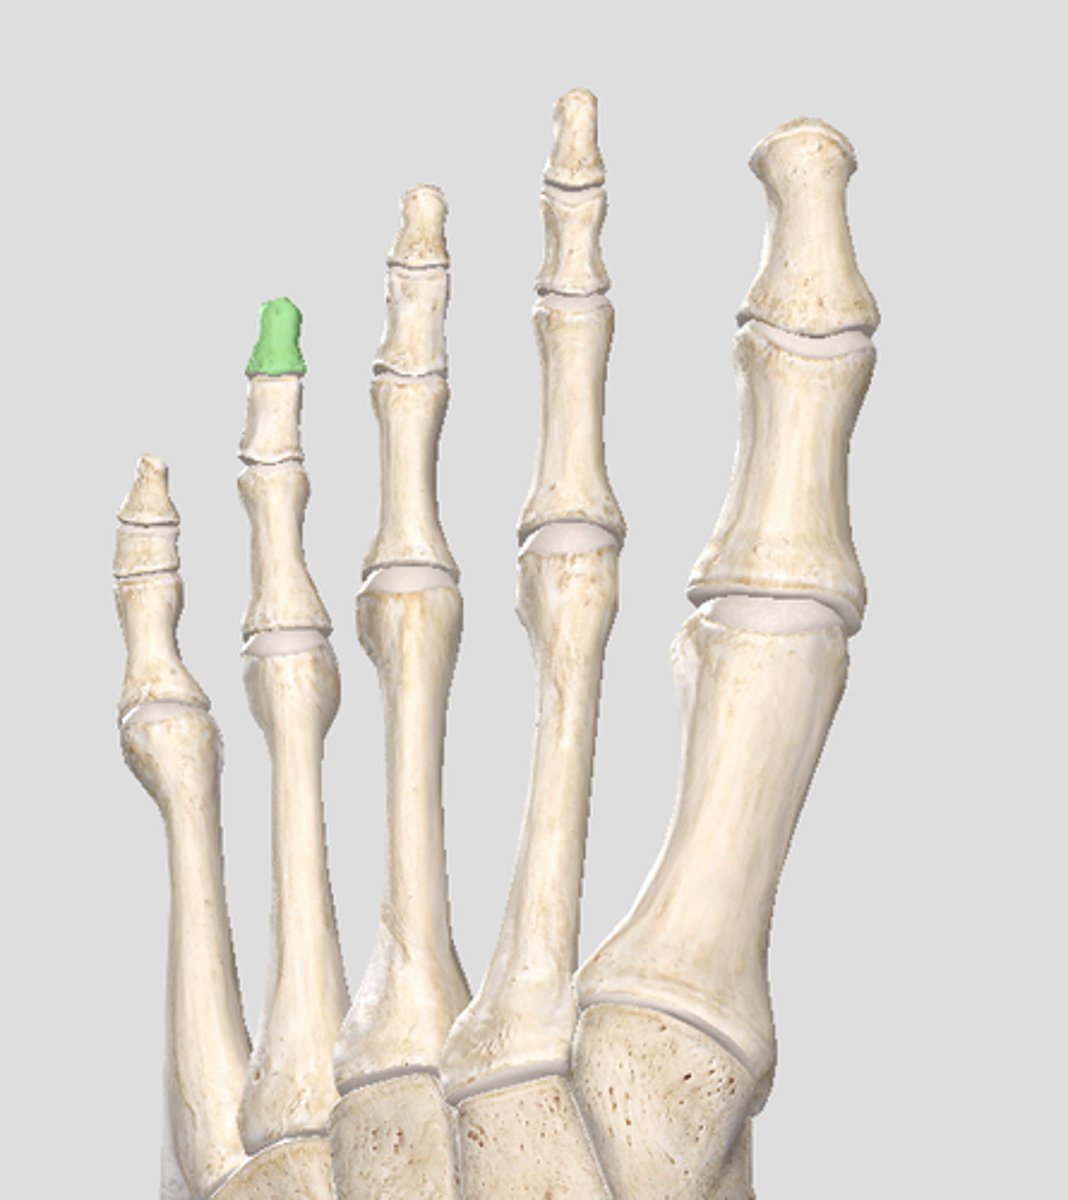

Distal phalanx of digit 2